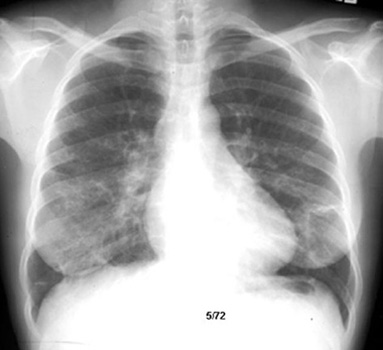

Progression from alveolar pattern to interstitial fibrosis (apparent "radiological improvement", but worsening physiologically)